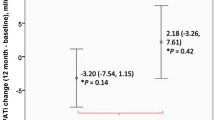

Correlation between EpF thickness and LVDD

The bivariate Pearson correlation coefficients for LV diastolic function parameters and EpF are shown in Figure 2. EpF was significantly associated with tissue Doppler e’, E/e’, and DT (r = −0.39, p < 0.001; r = 0.27, p = 0.001; r = 0.29, p < 0.001, respectively) (Figure 2A–C). EpF thickness was greater in patients with LVDD (n = 65; 5.1 ± 2.6 mm) than in controls (n = 84; 2.8 ± 1.6 mm, p < 0.001, Figure 2D).

Correlation between epicardial fat (EpF) thickness and left ventricular diastolic dysfunction (LVDD). EpF thickness correlated significantly with (A) e’ (r = −0.39, p < 0.001), (B) E/e’ (r = 0.27, p < 0.001), and (C) mitral inflow deceleration time (r = 0.29, p = 0.002). (D) EpF thickness in patients with or without left ventricular diastolic dysfunction (LVDD). The bar graph shows the mean + standard deviation. EpF thickness was significantly greater in patients with LVDD (5.1 ± 2.6 cm3) than in controls (2.8 ± 1.6 cm3, p < 0.001).